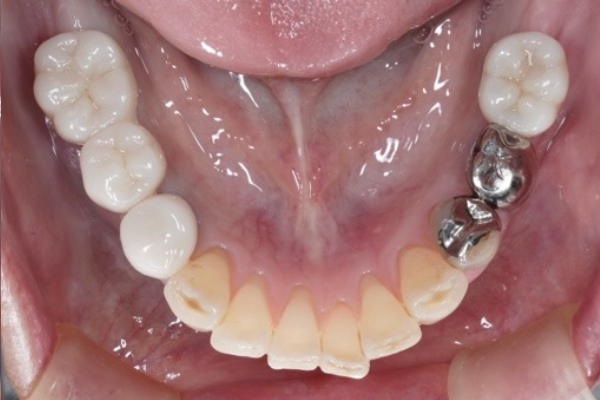

治療前(Before)

【治療前の状態(Before)】

歯根にヒビがあり保存不可でした。

奥歯欠損により咀嚼機能が低下していました。

入れ歯は希望されませんでした。